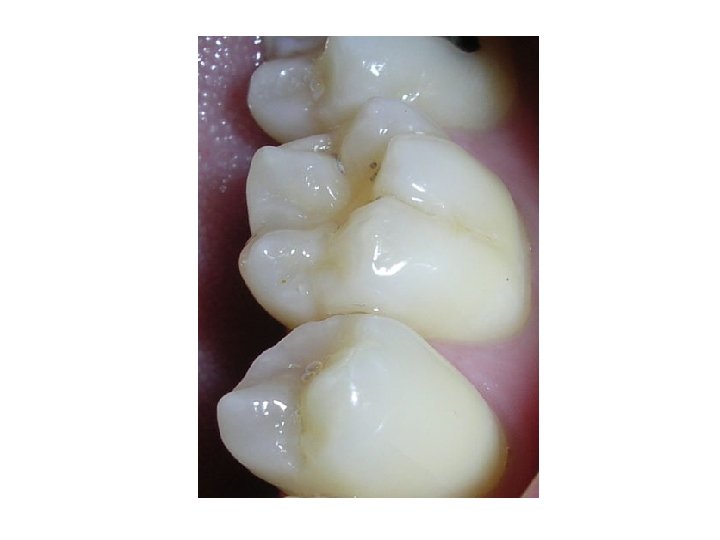

Detergent foods • Fibrous food in diet prevent lodging of food in pit and fissure and acts as detergent Chewing gum • Chewing gum tend to prevent caries by mechanical cleaning action Pit and fissure sealants • A sealant is a dental resin that is firmly bounded to enamel surface and isolates pit and fissure from caries producing conditions in oral environment • Types: 1 st generation – ultraviolet light activated 2 nd generation – chemical activated 3 rd generation – visible light activated 4 th generation – fluoride containing